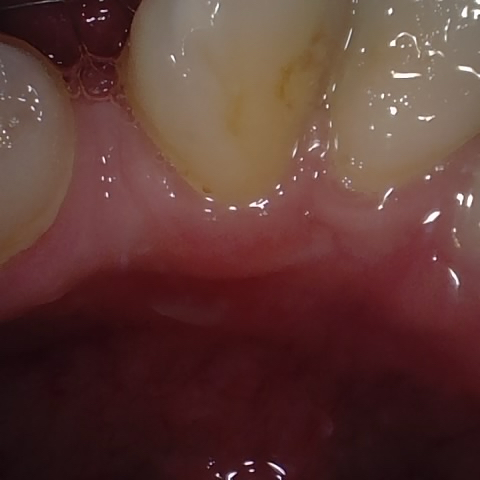

Annotated as "Bad"